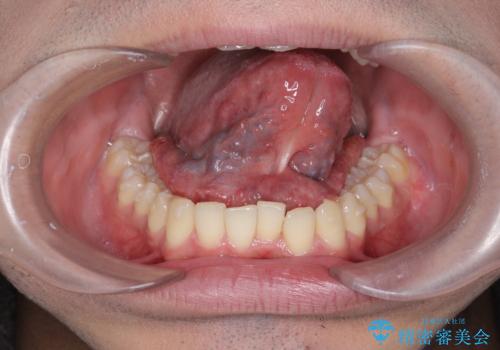

滑舌の改善 舌小帯の形成術

- 舌が動かしづらく、滑舌の改善を希望され来院されました。

舌小帯の形成術を即日で行い、1週間後に抜糸を行います。滑舌の改善を実感され、喜んでいただくことができました.

舌小帯の形成術は約10分程度で終了する小手術です。